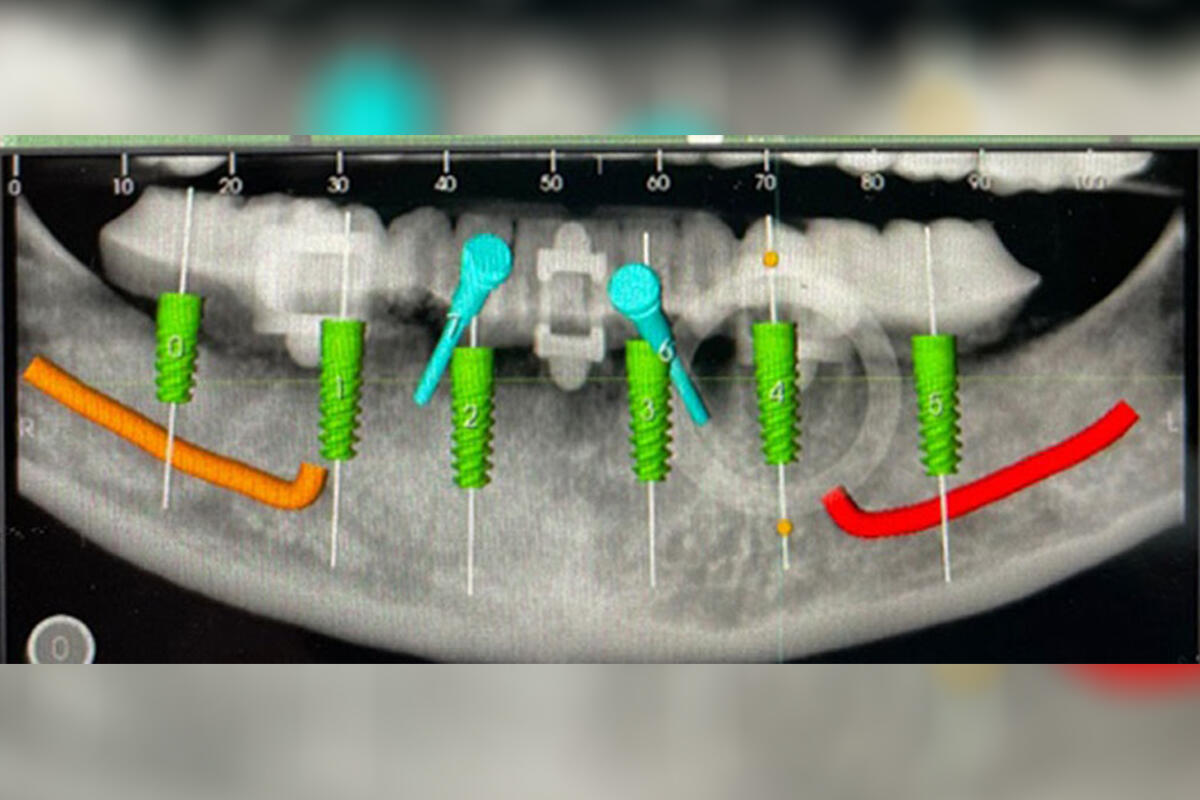

Unendo i dati di una TAC dei mascellari con quelli di una scansione della protesi del paziente, si possono digitalmente posizionare gli impianti sugli spessori ossei della TAC e creare una dima chirurgica, cioè una sottile struttura di resina trasparente, che serve al clinico per inserire gli impianti dentali con le corrette inclinazione e profondità. In questo modo l’applicazione della protesi risulterà più semplice.